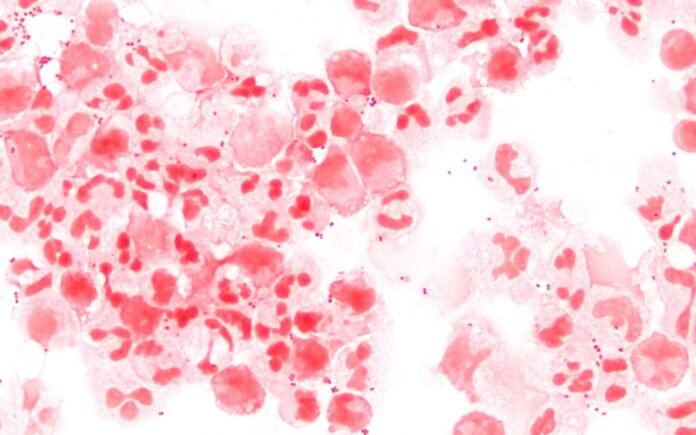

Conforme o Ministério da Saúde, a meningite é uma inflamação das meninges, membranas que envolvem o cérebro e a medula espinhal, podendo ser causada por bactérias, vírus, fungos e parasitas.